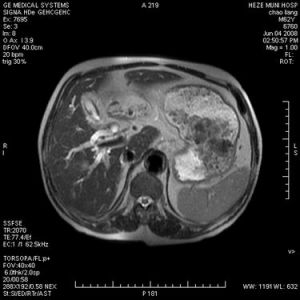

4、CT:膽管癌的CT基本表現為⑦顯示為膽管癌之近端膽管明顯擴張。接近腫瘤的膽 管壁增厚,於增強掃描時膽管更清晰可被強化,管腔呈不規劃的縮窄變形。一般可發現軟組織密度的腫瘤影,其CT值為50Hu,增強掃描時被強化CT值為60~80Hu。②腫瘤多數沿膽管壁浸潤性生長。膽管壁增厚,邊緣欠清晰,增強掃描時可被強化而易顯示。少數呈息肉狀或結節狀向管腔內生長,結節為軟組織密度。③腫瘤向腔處浸潤擴展,管壁邊緣模糊。常侵犯膽囊肝臟、毗鄰的血管及淋巴組織。而呈不均密度軟組織影,形態不規整,組織結構模糊,界限不清。